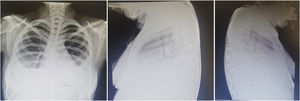

Diagnóstico. Puede corroborarse ante los hallazgos clínicos, el descenso no explicable de hemoglobina, hallazgos radiográficos característicos y la respuesta favorable al tratamiento. En la figura 4 se muestra radiografía con imágenes alveolares características de hemorragia alveolar. Algunas herramientas que pueden contribuir al diagnóstico son:

Mujer de 20 años con historia de lupus eritematoso sistémico de 4 años de evolución. Con vasculitis necrosante en miembros inferiores, psicosis, eritema, fotosensibilidad, trombocitopenia, linfopenia, anemia grave, VDRL+ y AAN 1:640 homogéneo y periférico. Últimos meses con disnea progresiva hasta la de mínimos; últimos días con incremento de tos, disnea y hemoptisis; hemoglobina 3g, hipoxemia, proteinuria nefrótica y sedimento telescopiado. Tele de tórax muestra imágenes alveolares compatibles con hemorragia alveolar difusa. Recibió metilprednisolona 1g 3 días y ciclofosfamida con adecuada respuesta.